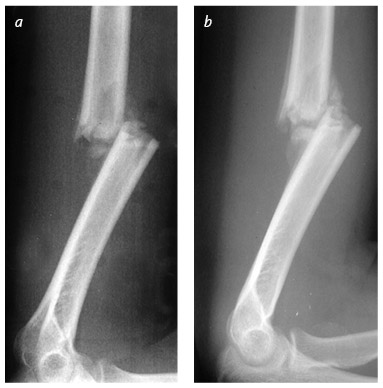

Вид сбоку показывает этапы заживления и перестройки кости при переломе плеча: на момент повреждения (a), через четыре недели (b), через восемь недель (c) и через шестнадцать недель (d), когда перелом хорошо зажил. Остеокласты притупляют острые углы, а остеобласты наслаивают новую костную ткань, стабилизируя перелом. Вместе эти строители и разрушители постепенно восстанавливают правильное расположение и форму кости